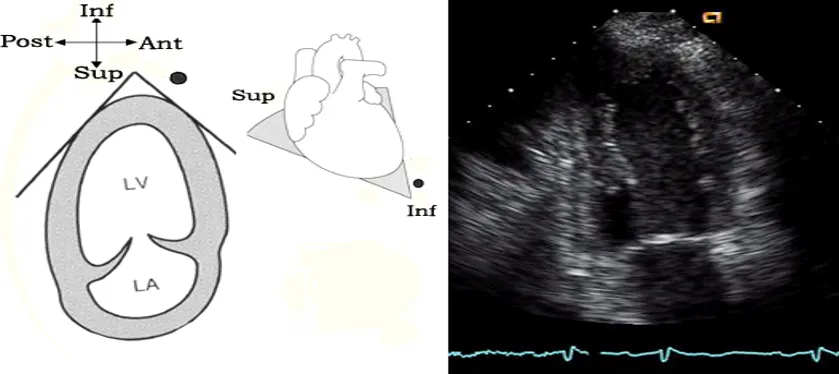

剑突下

● A为短轴切面,近似于人体矢状切面。

● B为长轴切面,近似于人体冠状切面。

剑突下四腔心切面

探头位置:探头位于剑突下声速指向左肩。

观察内容:4个房室腔;二尖瓣、三尖瓣、房间隔、室间隔。